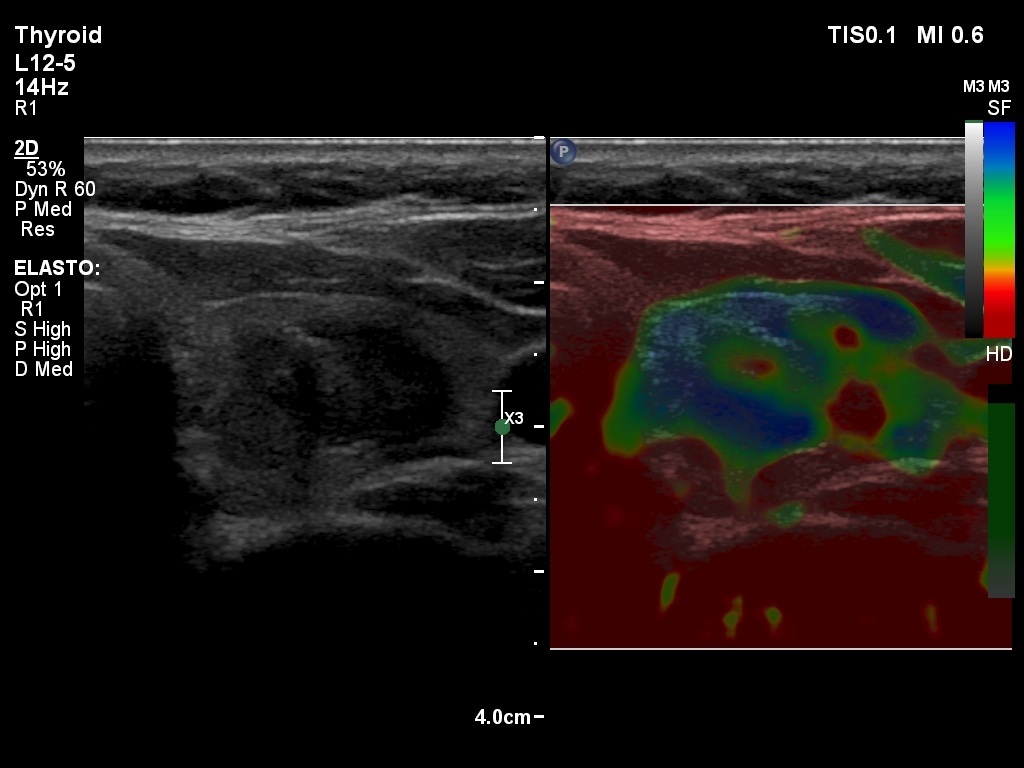

Second examination 2 years later (3rd row of images)

Ultrasonography: the ultrasound presentation of the thyroid was basically unchanged except for the presence of cystic area within the nodule. The vascularization and elastography of the nodule were not specific.

Suggestion: to continue the follow-up with ultrasound and TSH determinations every three years.